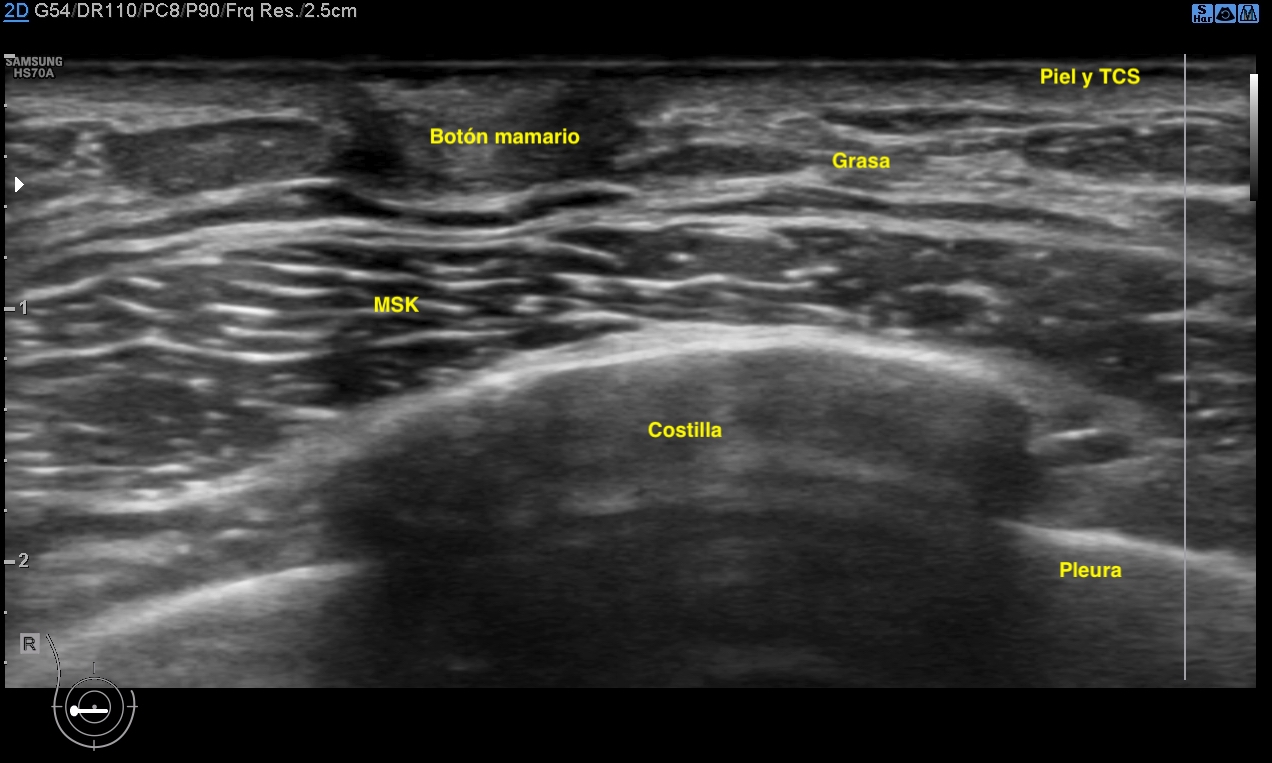

Siempre la anatomía normal. En la mujer tejido graso y tejido mamario conviven, en el hombre el tejido mamario no debe existir y tenemos que demostrar siempre la ausencia de este en el espacio retroareolar, principalmente. En la imagen 1 ves la relación de tejidos en un corte axial del pezón de la mama derecha masculina. Corresponde con la imagen número 2 ya sin anatomía.